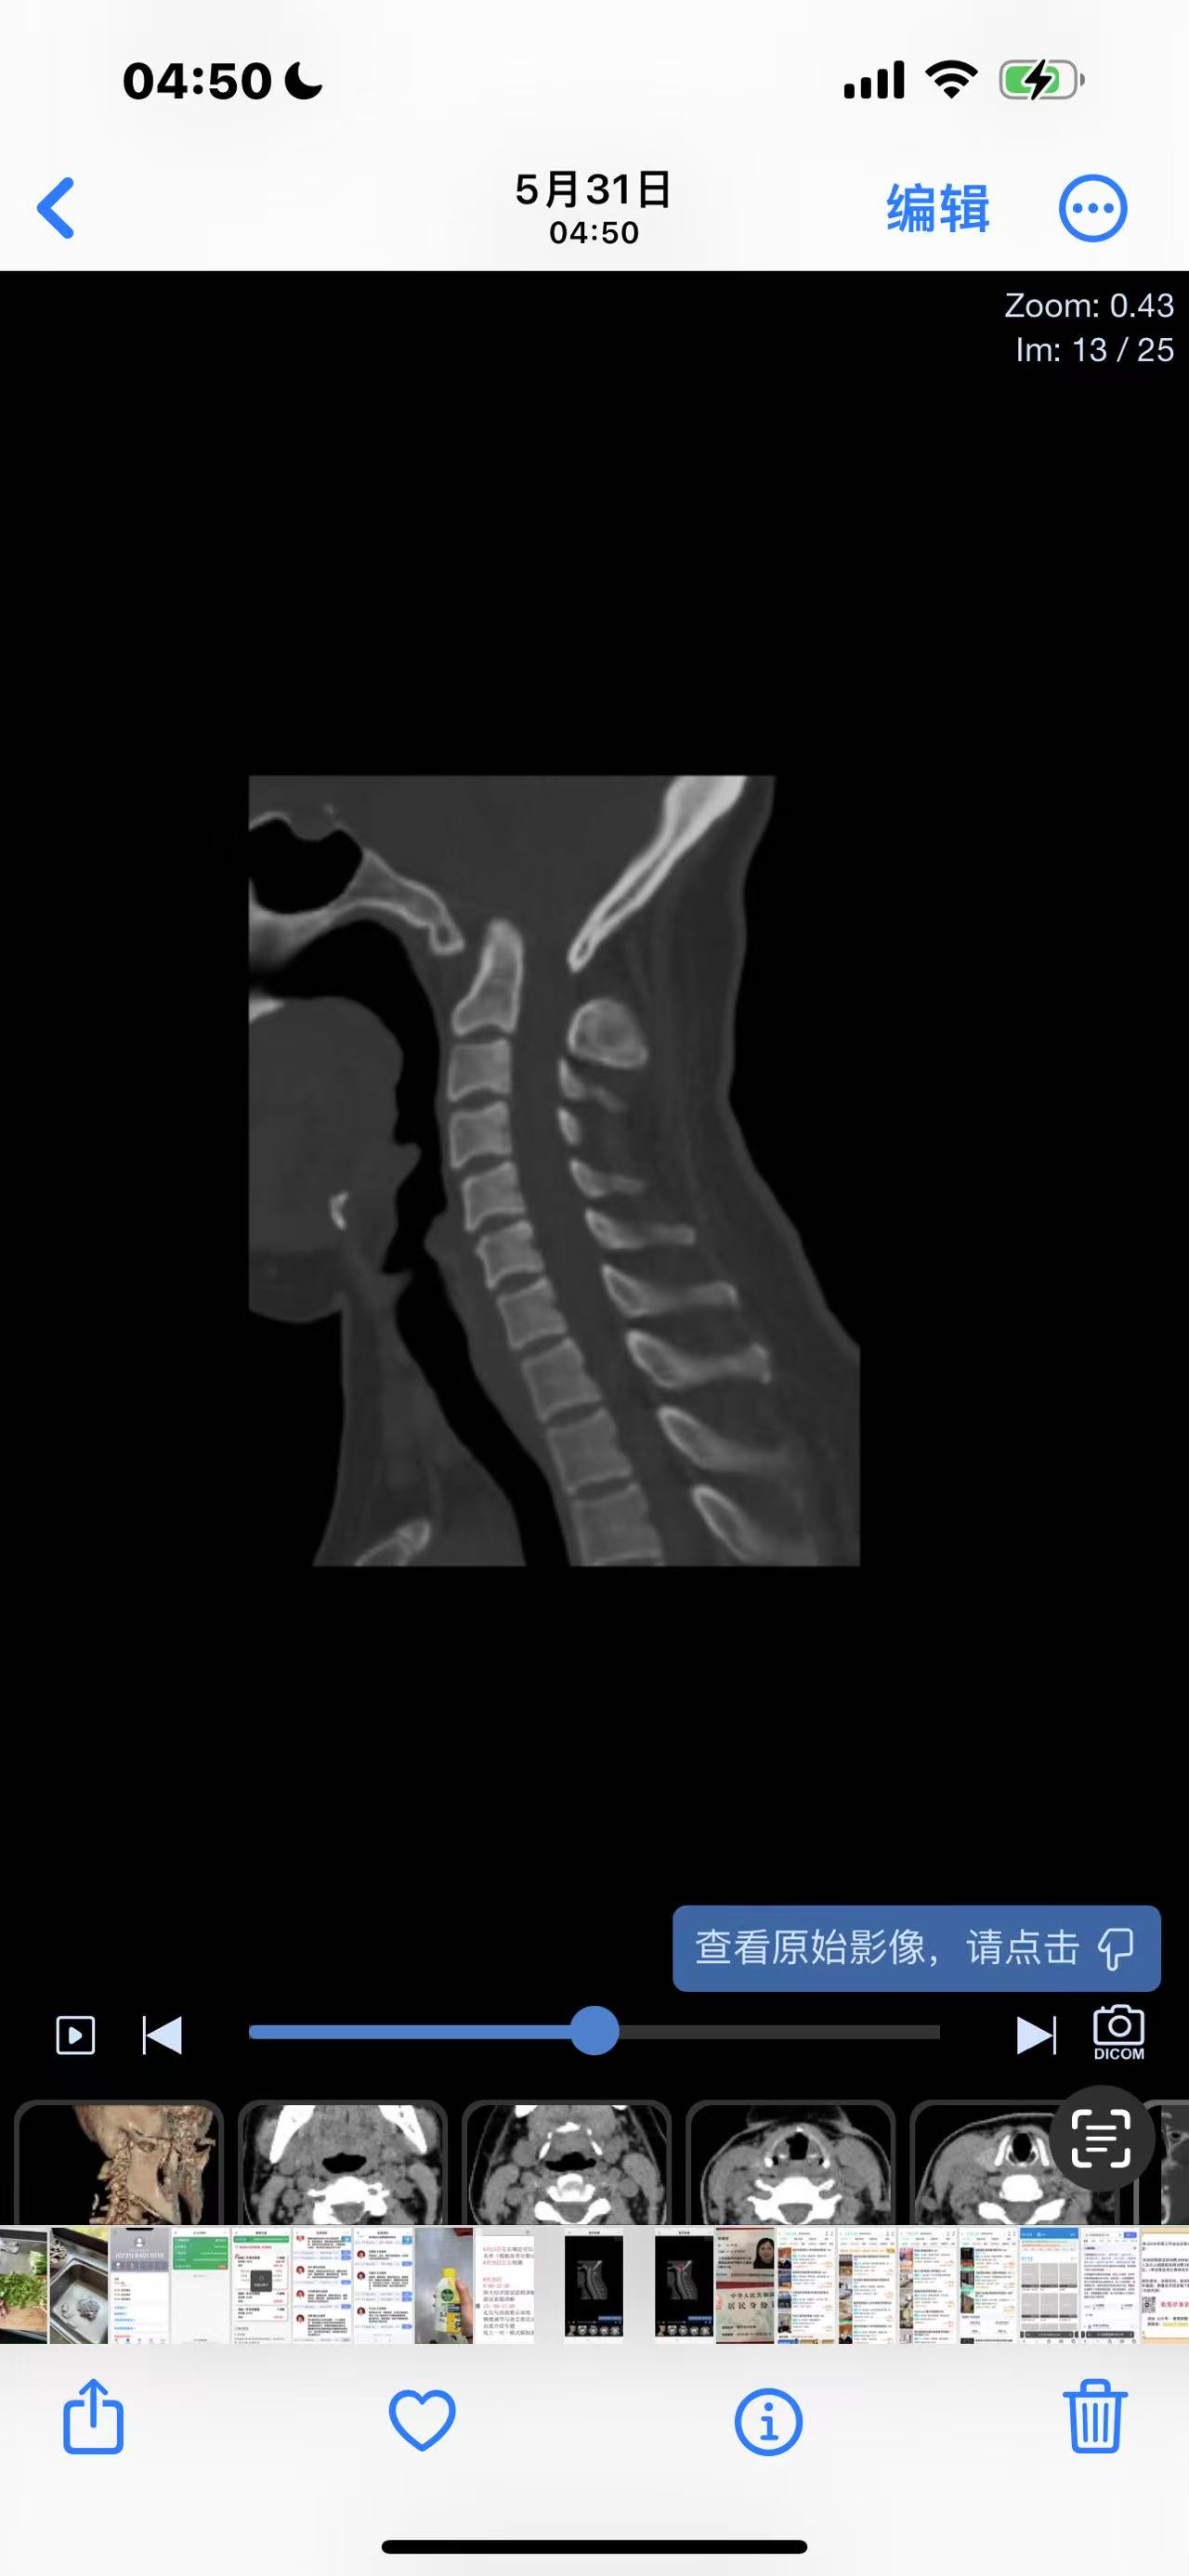

• 诊断:寰枢椎脱位

• 影像:

• 术后影像: